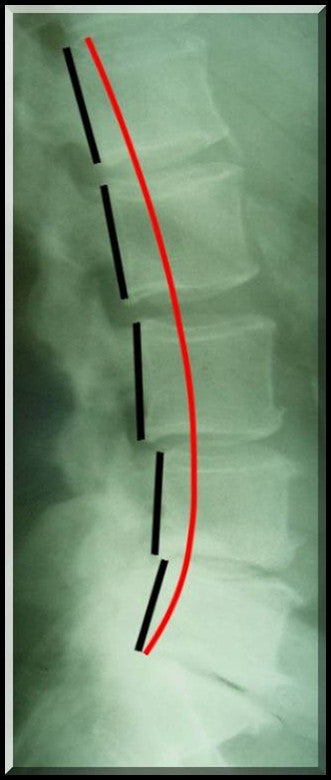

Ideal Curve Template for Lateral Lumbar X-rays. Based on Published in Journal of Orthopedic Research 1998 Distinguish between your patient's lordosis and the normal range with the Ideal Lumbar Elliptical Template. "Percentage Loss" sheet for calculating your patient's posterior tangent ARA measurement to a % loss from normal. This is part of an evidenced based report of findings.